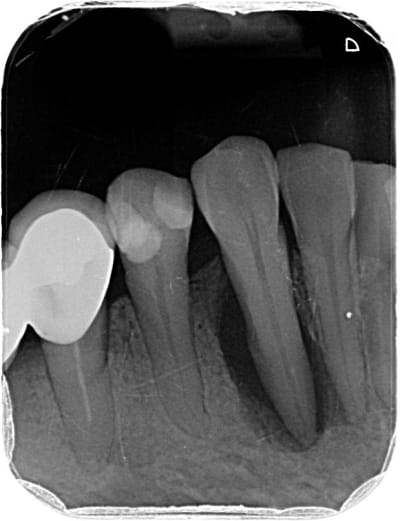

J'aimerais votre avis pour ce cas. Je suis sûre à 99% qu'il faille dévitaliser la 37 suite à pour moi un abcès apical aigu mais je ne trouve pas de réelle cause et j'aimerais savoir si vous aviez une idée.

09/06 : 37 a eu petite gene dernierement a la mastication très léger par moment. Tartre ++ en occlusal de 27 je pense à une sur sollicitation. Elargissement desmodontal sur la radio mais froid positif donc surement traumatique par surocclusion? Si perdure peut etre fracture? A ré évaluer.

07/07 37 : douleur type abcès apical aigu il y a 2 semaines calmées par les ATB. // Scan pour recherche origine fracture, RAS. Test au froid clairement négatif cette fois (on en a reparlé il lui semble vraiment qu'elle sentait le froid la fois d'avant... ) Mobilité 2 de la dent. Plus de tartre antagoniste. La patiente rapporte beaucoup bruxer, on fait donc une gouttière.

Elle est necrosee ca se voit sur la pano à l apex

Il n y a pas 500 possibilités il n y a pas de carie pas de fracture car pas d image en doigt de gant et de signe clinique de fracture ... il reste a mon humble avis que des surcharges de forces peut etre légères et répétées antérieures car pas de surocc a priori

Probable trauma, violent ou modéré mais chronique, ayant entrainé fêlure puis nécrose.

Je confirme l'avis de Thierry, les fêlures ne se voient souvent pas, pas plus à la radio 3D d'ailleurs.

Si test au froid négatif, l'image à la radio ne fait aucun doute: c'est nécrosé, faut dévitaliser.

J'ai constaté qu'avec cette morphologie de racine pour les 7 mandibulaires on avait un risque accru de fêlures fractures.